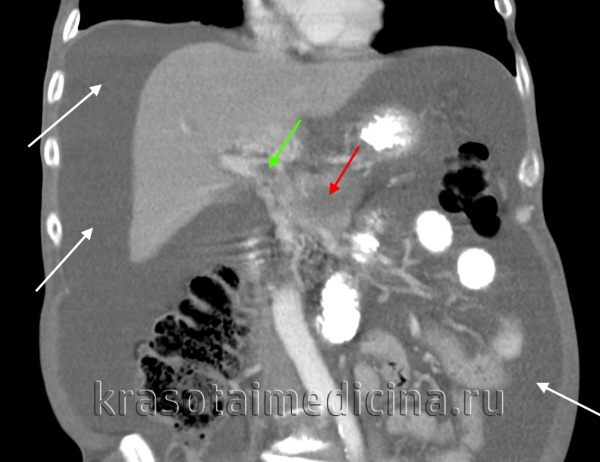

КТ ОБП. Портальная гипертензия на фоне обструкции воротной вены опухолью поджелудочной железы (красная стрелка). Опухолевый тромб (зеленая стрелка) в воротной вене. Асцит (белая стрелка).